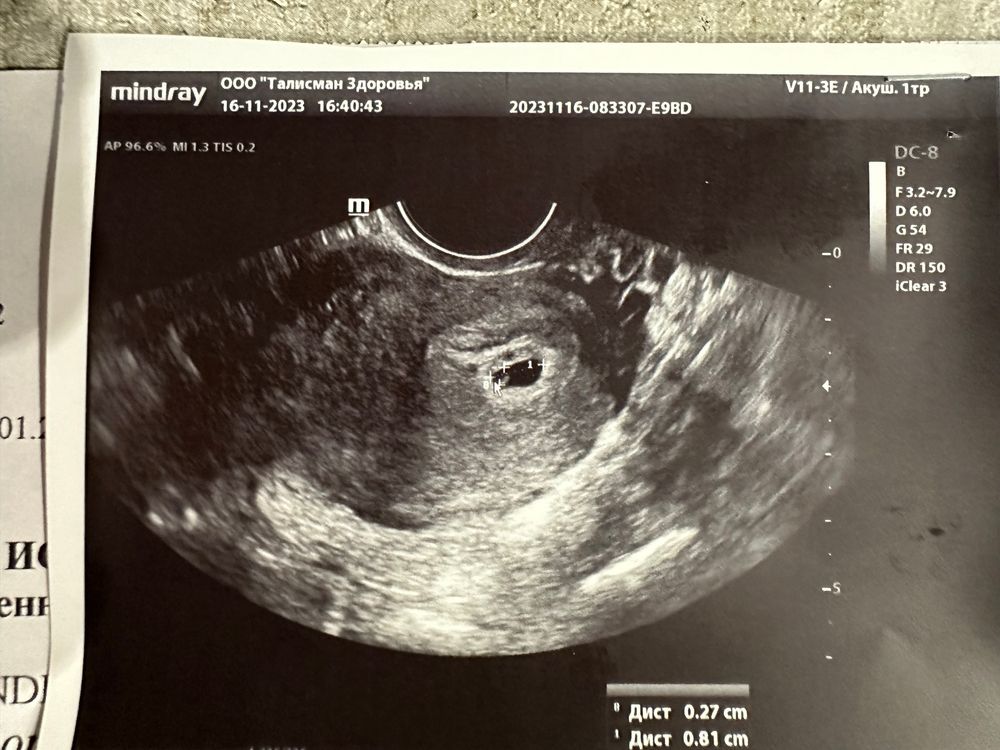

20дпп. Узи

От тонуса будет не круглое, но это не страшно. Папаверин,ношпа, магний. Тоже было и гематома и тонус, но на бОльшем сроке. Я на УЗИ тоже каждую неделю ходила)) мы такие))) мне на 21 дпп даже не стали разглядывать жм. Через неделю будет уже и эмбрион и сб.

Алёна, оооо, как жаль.... Вот и у меня кроме груди ничего не болит, на 22 дпп пя было 7,5, жм 3, сказали норм, ждём, на следующее УЗИ через 2 недели только, переживаю вот теперь....